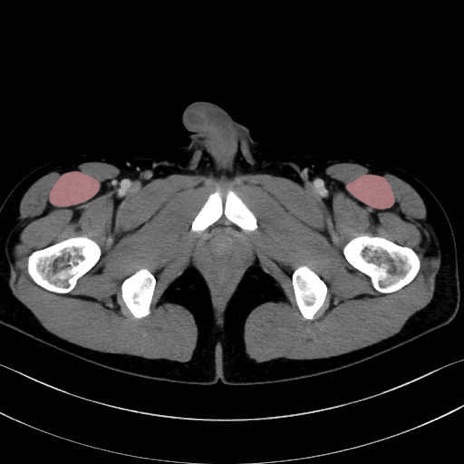

大腿直筋 (Rectus femoris)